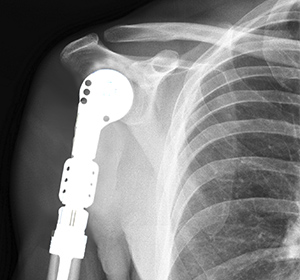

Some of the proximal humerus reconstruction and stabilization methods include allograft, endoprosthesis, megaprosthesis, alloprosthetic composite (APC), and more recently, reverse shoulder arthroplasty (RSA). The main objective of these methods is not only to reconstruct the resected bone segment, but also to restore a mobile and stable shoulder without any functional limitations.

There is no general agreement on the ideal method for reconstruction after resection. The choice of the method depends upon the condition of the soft tissues at the end of the resection. However, endoprosthetic reconstruction is the commonly employed technique for reconstruction of large proximal humeral defects.

- A trial prosthetic humeral head is then tested. The medullary canal is reamed in order to fit the stem of the prosthesis. The head, neck, and body of the prosthesis are assembled and matched with the resected proximal humerus. It is then fitted in place.

- Range of motion of the shoulder is then tested. If satisfactory, the final prosthesis is then precisely oriented and cemented into the medullary canal.